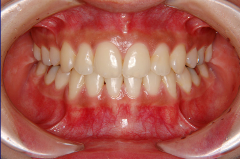

ステップ8.装着撤去&保定治療開始

ステップ9. 矯正治療終了